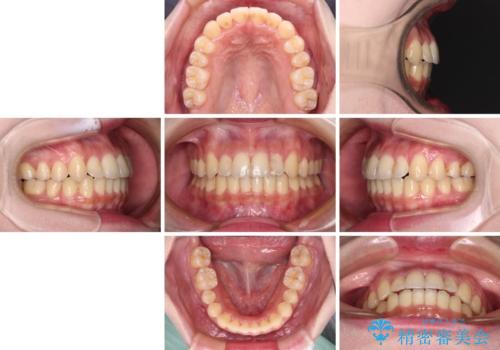

- 前歯のデコボコを気にして来院された患者様です。

上顎右側犬歯が八重歯になっており、それによって奥歯が前方に移動しているため、右側の咬み合わせの改善が必要と判断されました。

マウスピース矯正では改善に時間がかかる、あるいは改善しきれない可能性があることを伝えたところ、短期間で確実に治療ができるワイヤー矯正を選択されました。

より治療を速やかに行うため、上顎右側にアンカースクリューを使用し、目標としていた1年半ほどで治療を終えることができました。